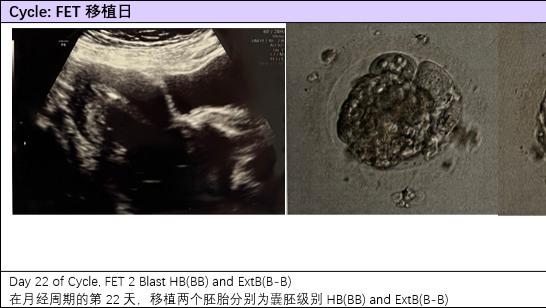

40岁+高龄夫妇移植成功,子宫肌瘤和卵巢囊肿依旧平稳上岸!